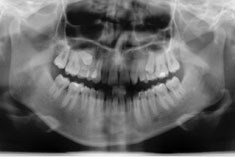

Die Nichtanlage der seitlichen oberen Schneidezähne und der zweiten unteren kleinen Backenzähne (Prämolaren) ist relativ häufig.

Wir verfügen über eine jahrzehntelange Erfahrung in der kieferorthopädischen Vorbehandlung, Implantologie und der prothetischen Versorgung von Nichtanlagen, sowie der Chirurgie und der Einordnung von verlagerten bleibenden Zähnen ohne den Einsatz von Implantaten.